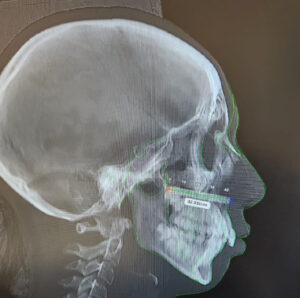

Jaw Surgery to Restore the Proportionality of the face

The field of Orthognathic surgery has been an ever advancing speciality striving to restore the facial harmony by surgical transformation...

Orthognathic Surgery in TMJ Patients

Corrective jaw surgery or Orthognathic surgery changes the structure of your jawbone and brings your upper and lower jaws into...

Best Orthognathic Surgery

Best Orthognathic Surgery At Richardsons Face Hospital

IntroductionCorrective jaw surgery, also known as Orthognathic surgery, changes the structure of your jawbone and brings your upper and lower...